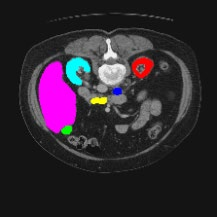

Transformers have made remarkable progress towards modeling long-range dependencies within the medical image analysis domain. However, current transformer-based models suffer from several disadvantages: (1) existing methods fail to capture the important features of the images due to the naive tokenization scheme; (2) the models suffer from information loss because they only consider single-scale feature representations; and (3) the segmentation label maps generated by the models are not accurate enough without considering rich semantic contexts and anatomical textures. In this work, we present CASTformer, a novel type of generative adversarial transformers, for 2D medical image segmentation. First, we take advantage of the pyramid structure to construct multi-scale representations and handle multi-scale variations. We then design a novel class-aware transformer module to better learn the discriminative regions of objects with semantic structures. Lastly, we utilize an adversarial training strategy that boosts segmentation accuracy and correspondingly allows a transformer-based discriminator to capture high-level semantically correlated contents and low-level anatomical features. Our experiments demonstrate that CASTformer dramatically outperforms previous state-of-the-art transformer-based approaches on three benchmarks, obtaining 2.54%-5.88% absolute improvements in Dice over previous models. Further qualitative experiments provide a more detailed picture of the model's inner workings, shed light on the challenges in improved transparency, and demonstrate that transfer learning can greatly improve performance and reduce the size of medical image datasets in training, making CASTformer a strong starting point for downstream medical image analysis tasks.